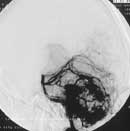

Рисунок. Левосторонняя вертебральная ангиограмма. Артериальная фаза. Артерио-венозная мальформация правого полушария мозжечка. (а) Фронтальная проекция.